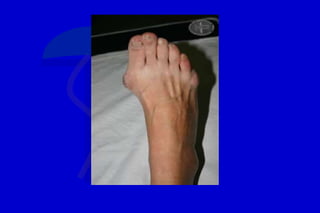

HALLUX VALGUS

Es una unidad compleja que involucra la

desviación lateral del dedo mayor con varo

del primer metatarsiano, considerado el

factor dominante

Desviación lateral del hallux, con varo del primer MT